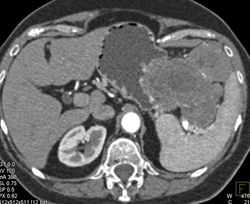

GIST Tumor